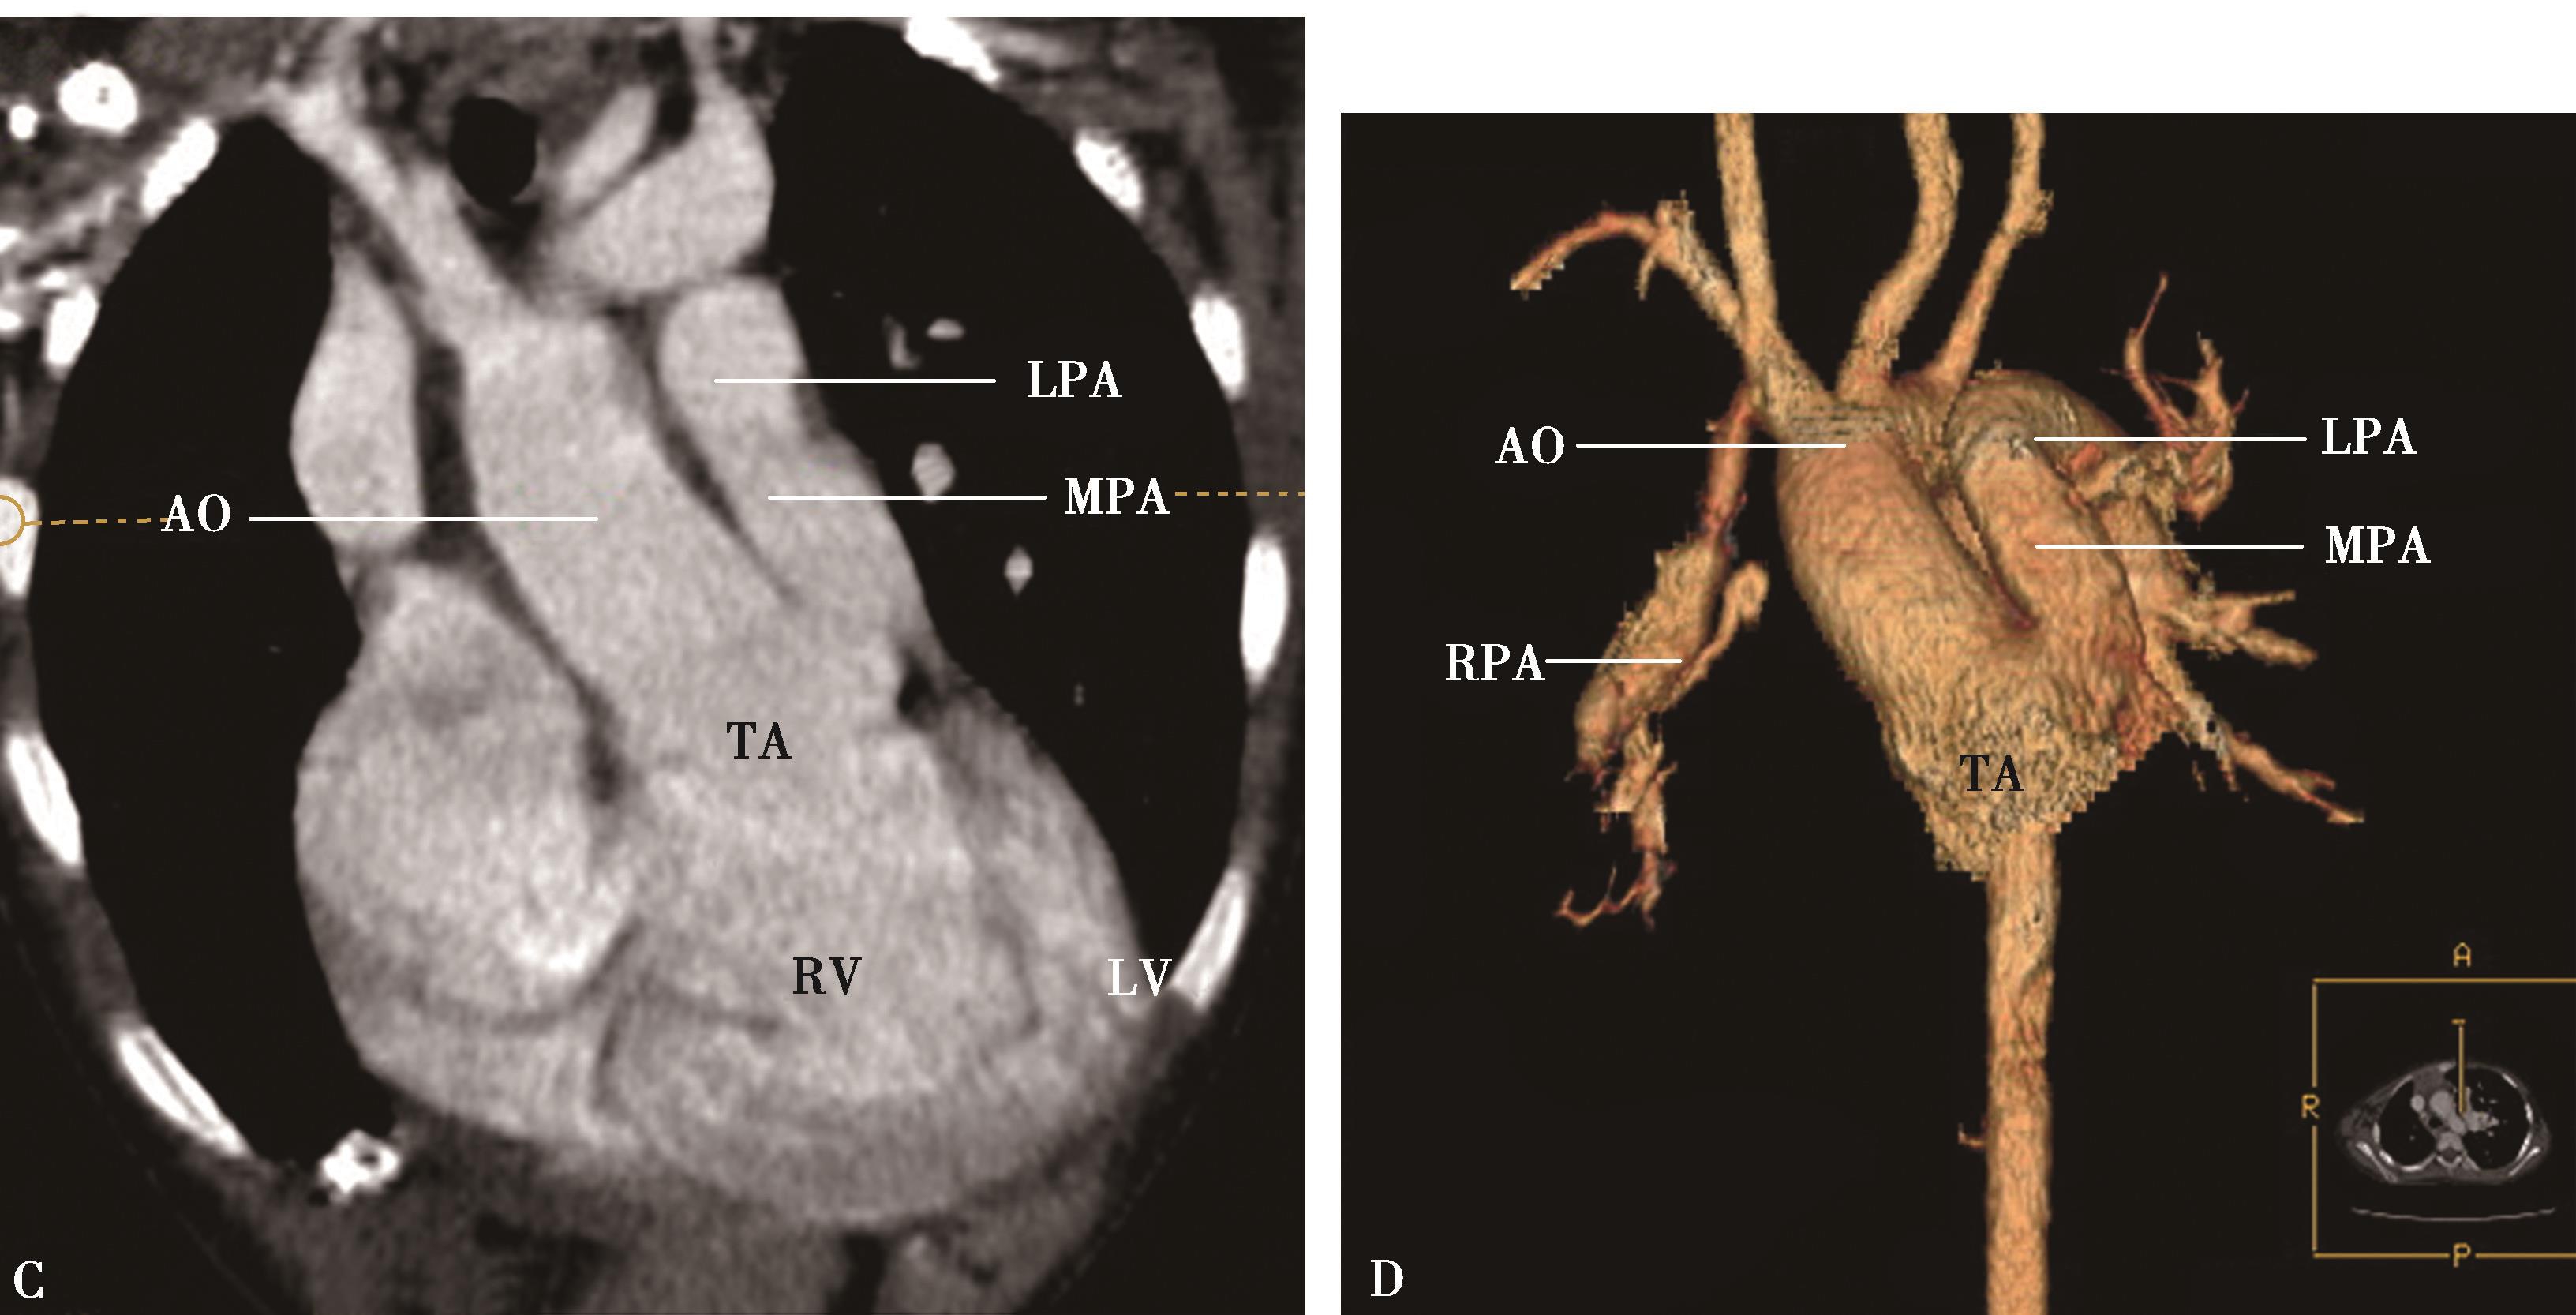

1)主肺动脉干或/和左右肺动脉干梭形瘤样扩张,腔内不同程度附壁血栓(图8-5-4)。

横断图像。A~C.主肺动脉、瘤样扩张,左右肺动脉瘤样扩张,不规则附壁血栓(↑);D~F.三维重建主肺动脉及左右肺动脉瘤样扩张,红色为附壁血栓(↑),波及肺叶分支;CT诊断:肺动脉瘤累及主肺动脉、左右肺动脉及叶分支,附壁血栓形成,病变性质考虑为白塞病